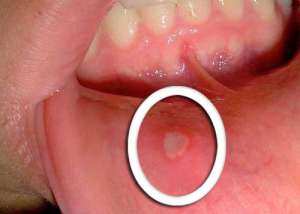

Objawami występowania owrzodzenia w jamie ustnej jest: pieczenie, bolesne mrowienie, okrągłe rany w kolorze białym lub szarym z zaczerwieniami na krawędziach. W przypadku owrzodzenia może też wystąpić gorączka, obrzęk węzłów chłonnych, itp.